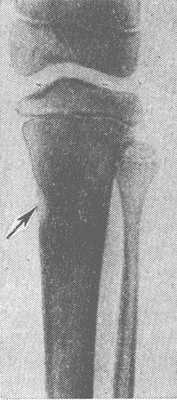

Рис. 1. Рентгенограмма голени: видна Лоозера зона в корковом слое большеберцовой кости в виде полоски просветления, имитирующей неполный перелом (указана стрелкой).

Рис. 2. Рентгенограмма голени: видна Лоозера зона перестройки диафиза большеберцовой кости, похожая на картину коркового абсцесса (указана стрелкой).

Рентгенол, симптоматика Л. з. весьма характерна, в особенности при локализации Л. з. в трубчатой кости. Сначала на рентгенограмме появляется едва заметная полоска просветления в диафизе с ровными контурами, пересекающая его в поперечном направлении. Крайне редко эта полоска может иметь косой или зигзагообразный ход. Вначале она может быть видна на одной стороне кости, создавая картину, сходную с неполным переломом (рис. 1), а в дальнейшем может распространяться уже на весь поперечник диафиза. К этому времени появляются более или менее обширные периостальные наслоения с обызвествлением, внешне аналогичные периостальной костной мозоли. Нередко на фоне периостальных наслоений полоска просветления едва прослеживается. Такая картина возникает часто в репаративном периоде заболевания. На отдельных этапах развития Л. з. могут возникать затруднения в диагностическом толковании рентгенол, картины, поскольку она формально может иметь сходство не только с переломом, но и с саркомой или корковым абсцессом кости (рис. 2). В целях дифференцирования особое значение приобретают повторные исследования.